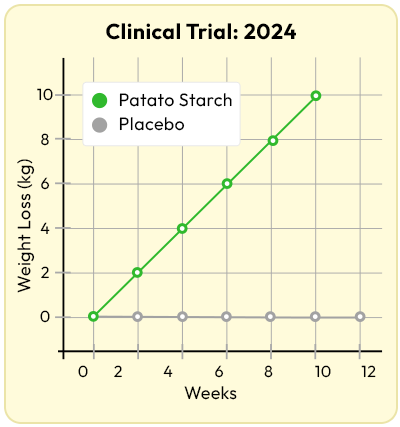

A brand-new 2024 clinical trial showed that participants taking potato starch…

Lost TWICE as much weight than those on a placebo.

Without changing their diet or exercise.

They lost over half a pound per week...

Consistently...

Just by adding this one compound.

The placebo group?

Zero change.

The difference was staggering.